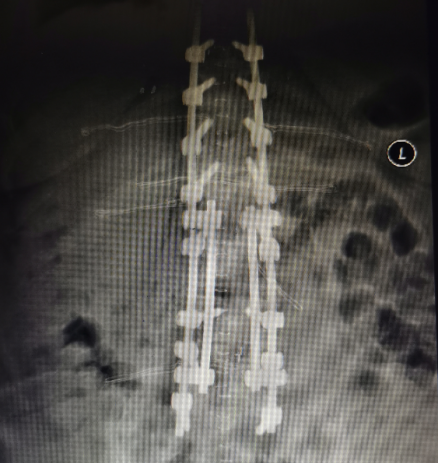

經(jīng)與眾多國內(nèi)頂級專家團(tuán)隊(duì)深入溝通,不斷創(chuàng)新,目前我司已形成了覆蓋全年齡、全術(shù)式的脊柱畸形解決方案。

德康醫(yī)療脊柱畸形解決方案

輕松完成連續(xù)節(jié)段壓棒提拉復(fù)位、矢狀位&冠狀位矯形、單節(jié)段&共平面去旋轉(zhuǎn)矯形